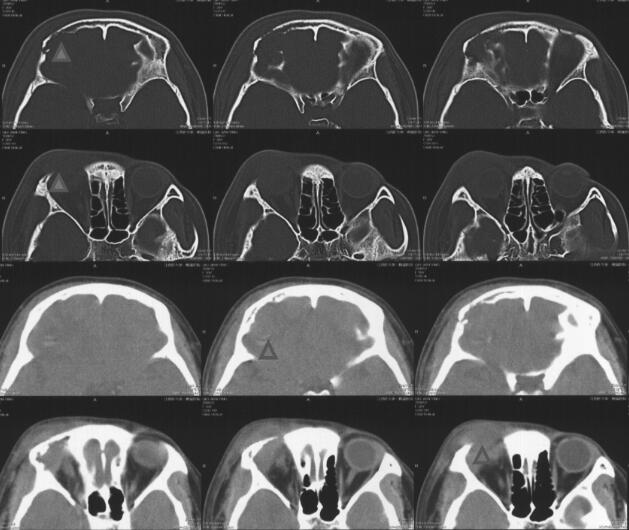

患者,女性,20岁,因“右眼肿痛,伴视物重影1个月,头痛1周”于2018年2月7日入院。2018年1月8日起无明显诱因出现右侧眼睑红肿、胀痛,伴右眼视物重影,无畏光、流泪、流脓,无视野缺损,后红肿逐渐加重,无法睁眼。2018年1月24日至当地医院,考虑“右眼上睑麦粒肿”,给予罗红霉素150mg每天2次,左氧氟沙星液滴眼,妥布霉素/地塞米松眼膏涂右眼,右眼红肿痛继续加重。2018年1月31日开始感右侧额顶部持续性胀痛,无头晕、耳鸣,无恶心、呕吐,无畏寒、发热,至当地医院复诊。行眼眶CT(图1)提示:额骨、眉弓范围软组织肿块伴骨质破坏吸收,并提示右大脑额叶脑水肿、出血可能,拟感染性病变首先考虑;头颅MRI(图2)提示:右侧额骨眼眶外上缘骨质破坏伴右侧额部、颞部、眼睑软组织及右眼上直肌肿胀,右侧额叶环形强化灶伴周围水肿,考虑感染性病变,其他病变待排。

图1 术前头颅CT示额骨、眉弓范围软组织肿块伴骨质破坏吸收